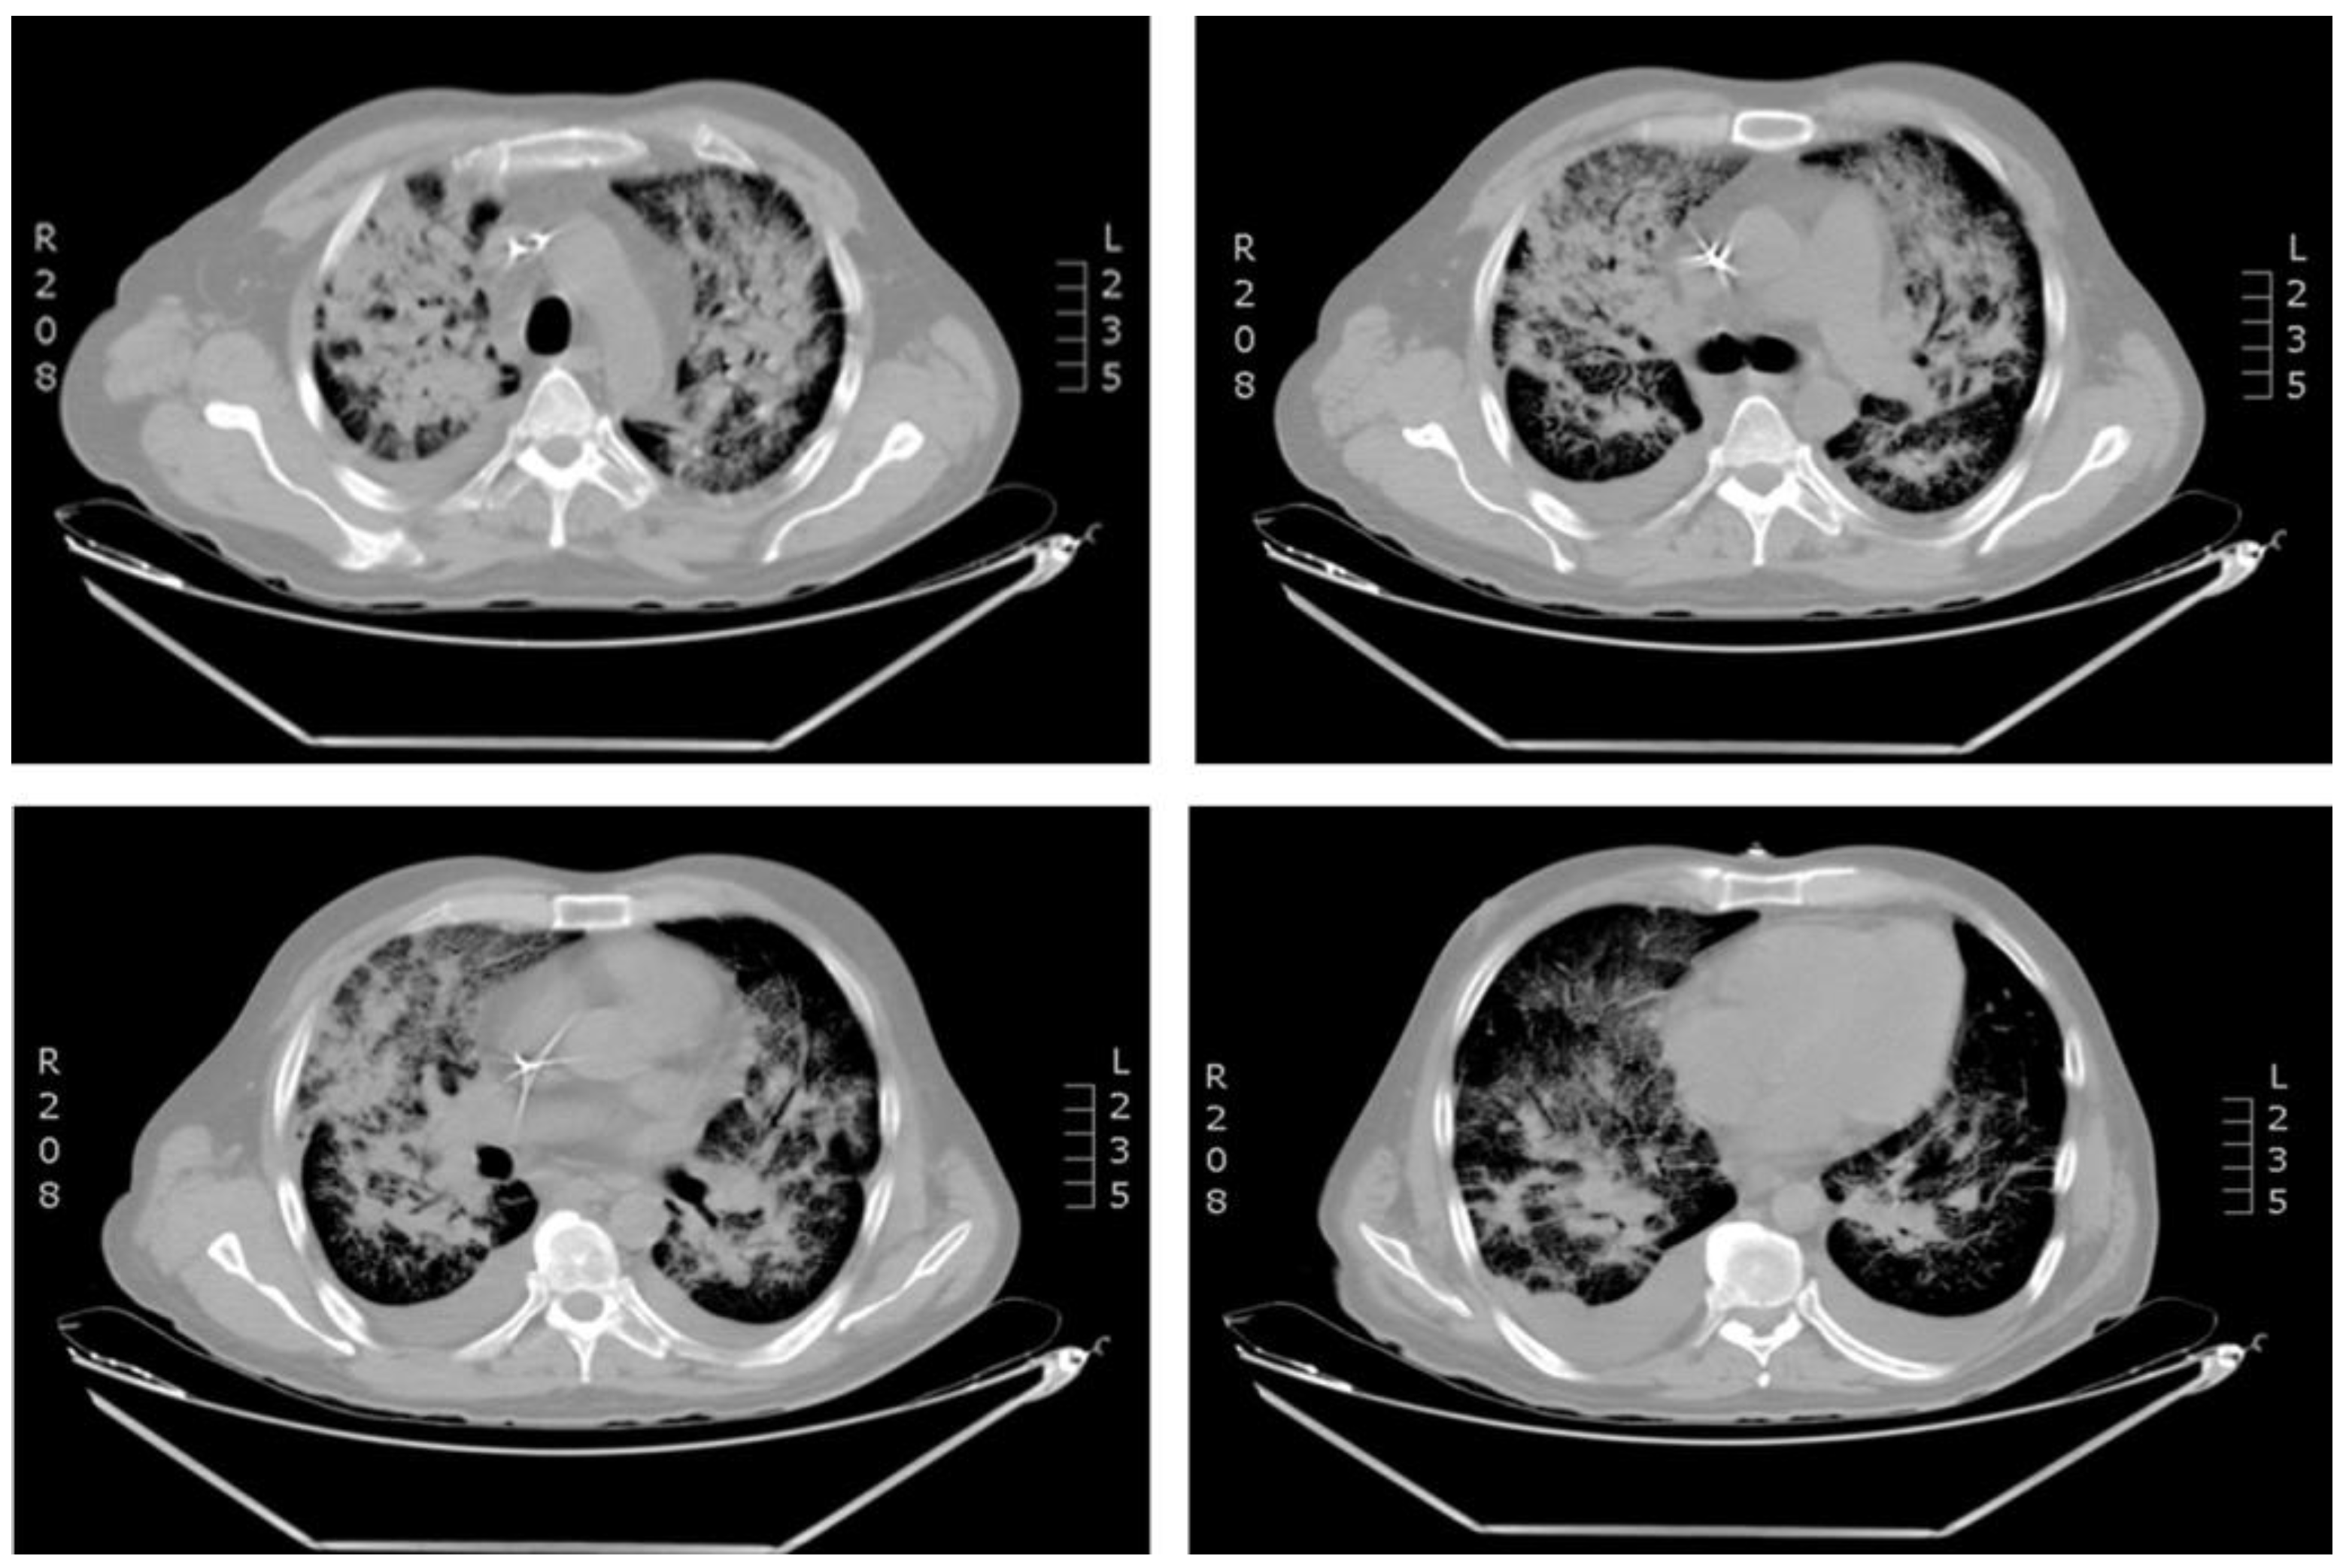

A 44-year-old Colombian man was admitted in a third level Clinic in Cali, Colombia at the end of February 2021 (rainy season). The patient had been diagnosed with acute lymphoblastic leukemia (ALL) two years previously, with history of two relapses. He referred five days of fever with no apparent cause. He had been treated with blinatumomab as a bridging therapy to stem cell transplant (SCT) and had finished the first month of treatment with blinatumomab ten days previously. Physical examination showed generalized paleness with normal vitals. At the time of admission, the patient was conscious and did not present urinary or respiratory symptoms. Pancytopenia was observed (Table 1). Blood transfusion of irradiated red blood cells and platelets was indicated; however, the pancytopenia did not improve, and other blood transfusions were required. Blood cultures were obtained and treatment with meropenem was initiated due to febrile neutropenia. Twenty-four hours after admission, the patient began to present respiratory symptoms, oxygen desaturation up to 60%, occasional cough, tachycardia, and hypotension. Treatment with vancomycin, amikacin and fluconazole was started. Chest X-ray showed increase in cotton wool opacities with commitment of all quadrants associated with bilateral broncho-pneumonic infiltrate in the consolidation process (Figure 1). Treatment for influenza virus (oseltamivir), Pneumocystis jirovecii (trimethoprim/sulfamethoxazole) and atypical bacterial infection (iv clarithromycin) was indicated, and COVID-19 was suspected. PCR and antigen detection in nasopharyngeal aspirate for SARS-CoV-2 were negative. Multiplex molecular detection of microorganisms (FilmArray, Biofire, USA) was requested. The patient continued presenting a rapid deterioration of his general condition with worsening of the respiratory pattern, desaturation, and severe hypoxemia, requiring non-invasive mechanical ventilation (the patient refused intubation). A CT scan of the lungs revealed severe bilateral bronchopneumonia, inflammatory hilar ganglia, and minor pleural effusion (Figure 2). Microbiological tests for bacteria, fungi, and mycobacteria were negative, but FilmArray was positive for coronavirus HCoV-NL63.There was no obvious contact with other people infected with HCoV-NL63. There is no specific treatment for this virus infection, thus supportive treatment was continued. Owing to the treatment with blinatumomab, secondary antibody deficiency was suspected, and humoral immune response was evaluated. Protein electrophoresis and serum immunoglobulins(IgG, IgA and IgM) levels revealed severe hypogammaglobulinemia (Table 1). Replacement therapy with intravenous immunoglobulins (IVIG) at a dose of 400 mg/kg (every 28 days) was indicated. Interestingly, the patient improved oxygenation diminishing supplementary oxygen requirement after only 24 hours from IVIG administration. The clinical evolution was adequate and the respiratory syndrome improved after 72 hours from IVIG administration (second molecular testing was not available). Treatment with blinatumomab was restarted. After the second dose of IVIG, his general health condition was good, and the patient was discharged. Currently the patient shows a good engraftment after 6 months from stem cell transplant with matched sibling donor, but he is still requiring IVIG due to hypogammaglobulinemia persistence (data not shown).

Figure 2.

Computed tomography (CT) scan of the chest revealing bilateral bronchopneumonia.